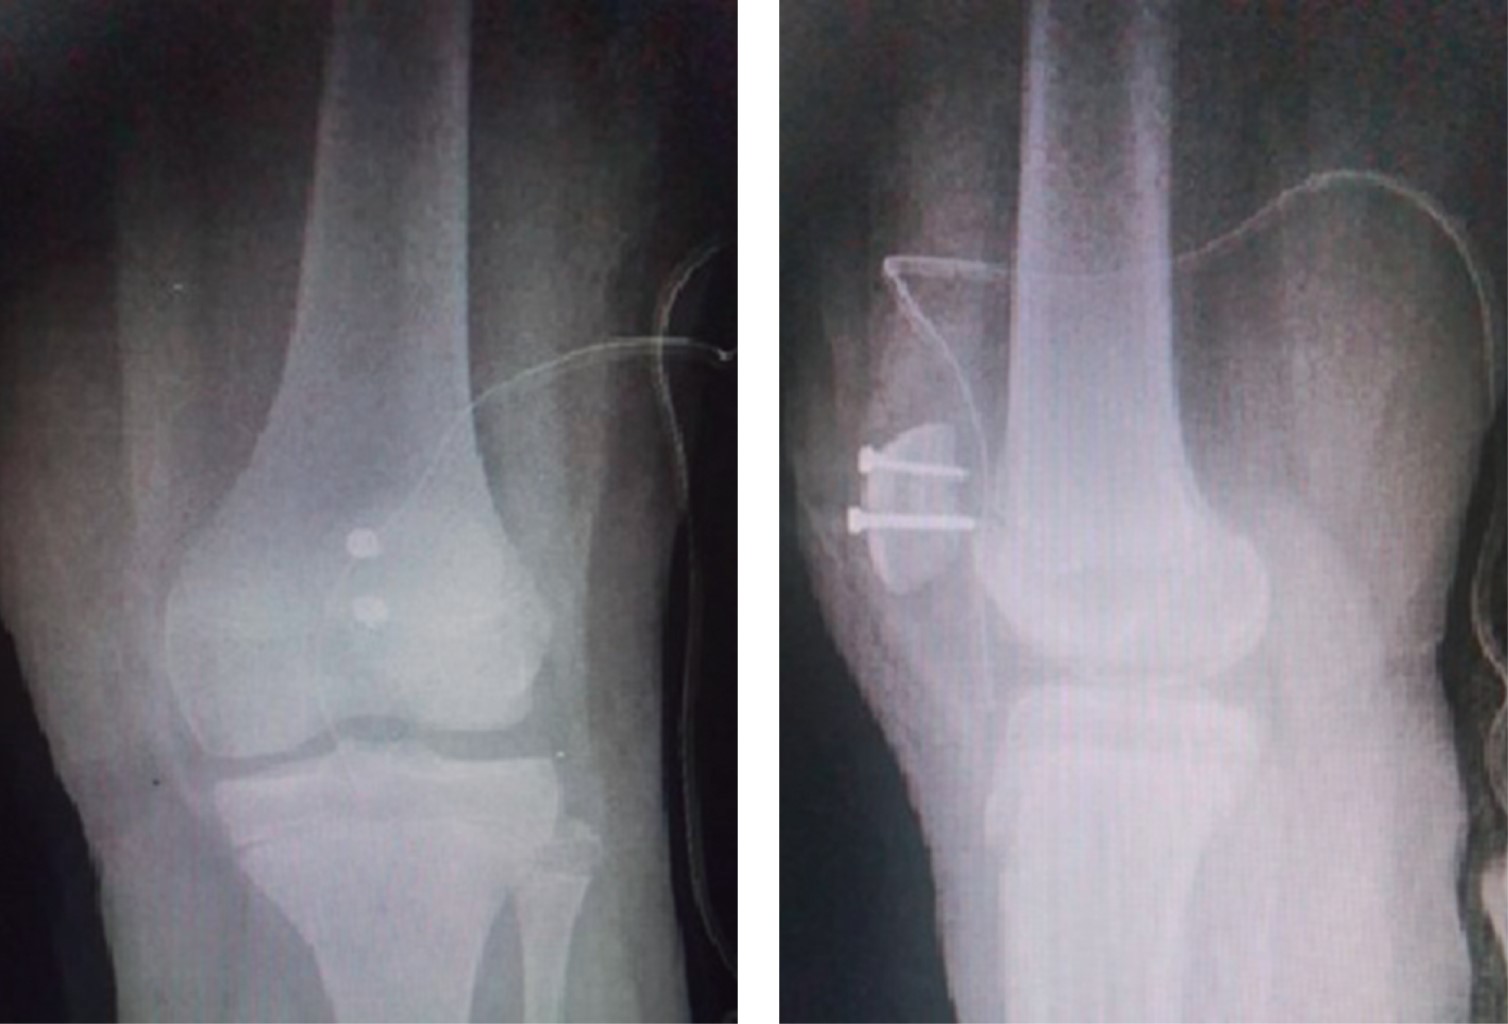

Se realizaron radiografías anteroposterior y lateral de rodilla izquierda 1 que mostraron leve aumento de los tejidos blandos, con presencia de fractura a nivel de la patela, con trazo simple coronal, fragmento desplazado hacia proximal y lateral que da la apariencia de doble rótula. Se decidió su ingreso para protocolo y tratamiento quirúrgico (Figura 1).

El paciente fue inmovilizado provisionalmente con férula muslo podálica y, al sospechar de alguna otra lesión oculta, se solicitó tomografía axial computarizada (TC) simple de rodilla izquierda con reconstrucción 3D. Se continuó con la imagen de doble rótula en la proyección anteroposterior y se corroboró sólo el trazo coronal (Figura 2).

Figura 1

Figura 2